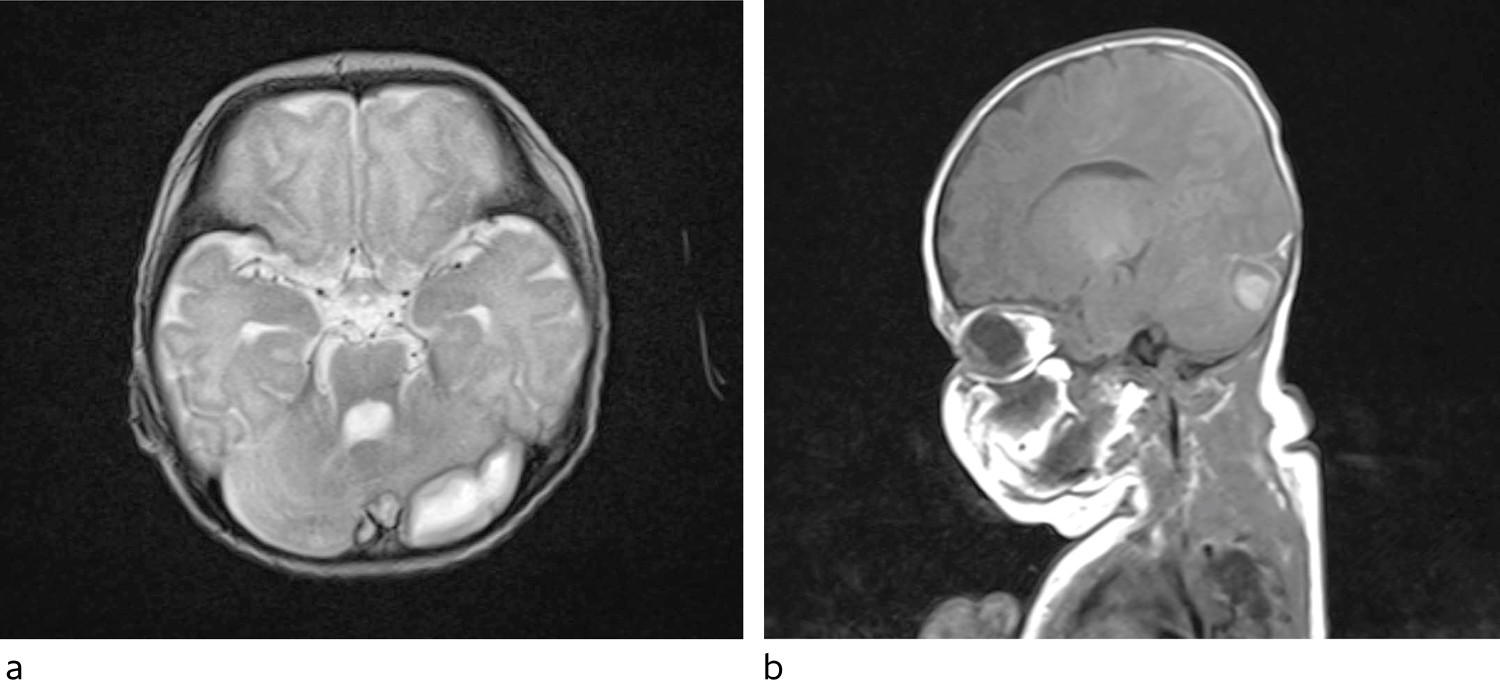

Klinisk var tilstanden stabil de påfølgende dagene. Det ble tatt daglige blodprøver, og CRP steg igjen til 180 for så å holde seg stabil i underkant av 200. Kroppstemperaturen var fortsatt svingende, og pasienten hadde gode perioder, men var også trøtt og sov mye. Det hadde blitt tatt ultralyd caput tre ganger i forløpet. De to første undersøkelsene viste tegn på ventrikulitt, den tredje var i det vesentlige normal. På bakgrunn av vedvarende høy CRP og fortsatt feber en uke ut i forløpet ble det besluttet at det var indikasjon for MR caput/columna med spørsmål om abscesser. MR-undersøkelsen viste omfattende trombosering av vener og venesinus samt flere abscesser (figur 1), hvorav den største ble målt til 3 × 1,2 × 1,3 cm. Det ble startet med enoksaparin som trombosebehandling (4,5 mg × 2 subkutant, gradvis justert opp til 7,5 mg × 2 monitorert etter anti-faktor Xa-verdi).

Ultralyd caput er den foretrukne billedundersøkelsen hos nyfødte med meningitt, og anbefales for alle hvor dette mistenkes. Undersøkelsen har høy sensitivitet for å avdekke ventrikulitt, hjerneødem og økt intracerebral væske. Imidlertid er MR overlegent når det gjelder forandringer i hjernevev, som f.eks. ved abscessdannelse. Dette gjelder særlig forandringer i bakre skallegrop (10). Hos vår pasient var det subtile tegn til ventrikulitt på ultralyd caput, men dette var i bedring tredje gang undersøkelsen ble utført. Ventrikulitt kan forhindre drenasje av cerebrospinalvæske og fører ofte til at den inneholder bakterier lenger enn ved meningitt uten ventrikulitt. I noen tilfeller kan ekstern drenasje og direkte instillasjon av antibiotika i ventriklene bli aktuelt. Det ble ikke vurdert i vårt tilfelle. Det var ikke mulig å se abscessutviklingen på ultralydundersøkelsene, verken den store abscessen beliggende over venstre cerebellarhemisfære eller de mindre abscessene langs venstre temporallapp. Det var heller ingen mistanke om venetrombose på ultralyd.

Ved utskrivelsen ble foreldrene instruert i måling av hodeomkrets og anbefalt å gjøre dette ukentlig. Allerede ti dager senere var økningen større enn forventet, og jenta ble tatt inn poliklinisk til nevrokirurg for vurdering av hydrocefalusutvikling. Hydrocefalus ble bekreftet billeddiagnostisk, og 16 dager etter utskrivelse fikk hun operert inn en ventrikuloperitoneal shunt uten komplikasjoner.